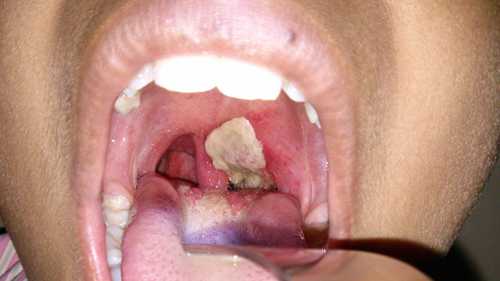

Người mắc bệnh bạch hầu.